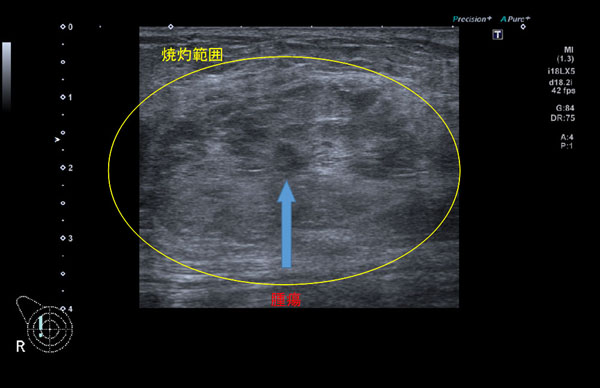

早期の「乳がん」治療で新たな選択肢 乳房を切らないラジオ波焼灼療法が23年末から保険適用で実施

術後の経過は順調。腫瘍はほとんど見えなくなるほどに(中部国際医療センター提供)